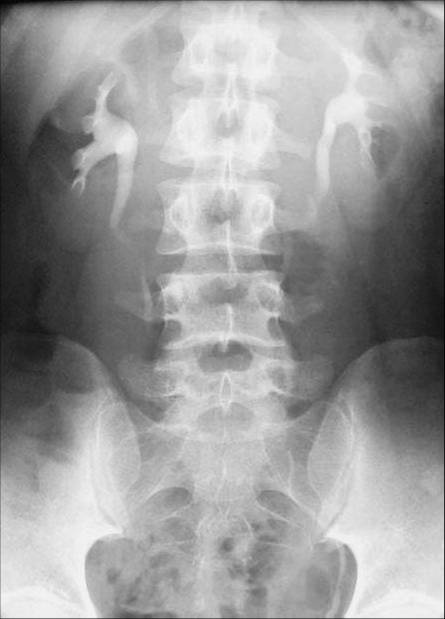

照片名称:静脉尿路造影